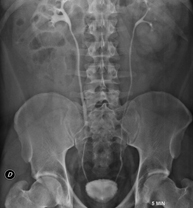

- Abdomen i pelvis

- RX Abdomen

Tècnica que usa els raigs X a través de la qual s'obtenen imatges de l'abdomen (estómac, intestí prim, intestí gros, fetge, ronyons, bufeta, pelvis òssia, etc.) per al seu estudi. - RX Columna lumbar

Una radiografia d'abdomen és una tècnica mitjançant la qual, amb l'ús d'una petita dosi de radiació, s'obté una imatge bidimensional de l'abdomen amb les seves estructures anatòmiques (estómac, intestí prim, intestí gros, fetge, pàncrees, ronyons, bufeta, pelvis òssia, etc.) - Telerradiologia columna